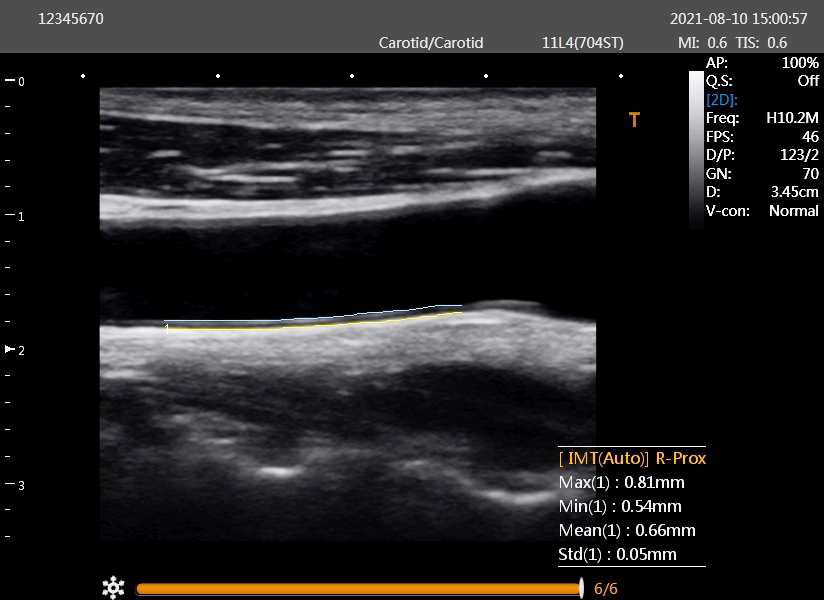

首筋にある太い血管を超音波法で調べます。実際に血管を観察することで、血管の壁の厚さや、血管の内側におできのような膨らみ(プラーク)ができていないか、血管が詰まっていないかなどを調べます。